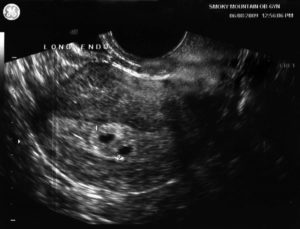

Фото узи 4 недели беременности двойня

При первом осмотре в 4-6 недель гинеколог не сможет определить количество плодов. Это видно на УЗИ только с 8 акушерской недели беременности (при условии хорошего аппарата у врача). До этого срока невозможно точно сказать многоплодная у вас беременность или нет.

Фото УЗИ двойни на ранних сроках беременности, 8 недель

В 8 акушерских недель (или 6 недель от момента зачатия) обычно используют трансвагинальный способ УЗИ. Аппарат вводят внутрь, чтобы лучше разглядеть эмбрионы. На мониторе видны два или три темных пятна. Врач измеряет длину зародышей и фиксирует несколько сердцебиений.

Следовательно, наличие двойняшек в утробе выявляется посредством ультразвука уже через месяц после зачатия, на снимке они выглядят как 2 образования темного цвета внутри полости матки (см. фото УЗИ-обследования двойни ниже).

Увидеть двойню на УЗИ при беременности можно уже через месяц после зачатия. В этом случае специалист отметит на экране монитора два пятна черного цвета, которые хорошо просматриваются ультразвуком